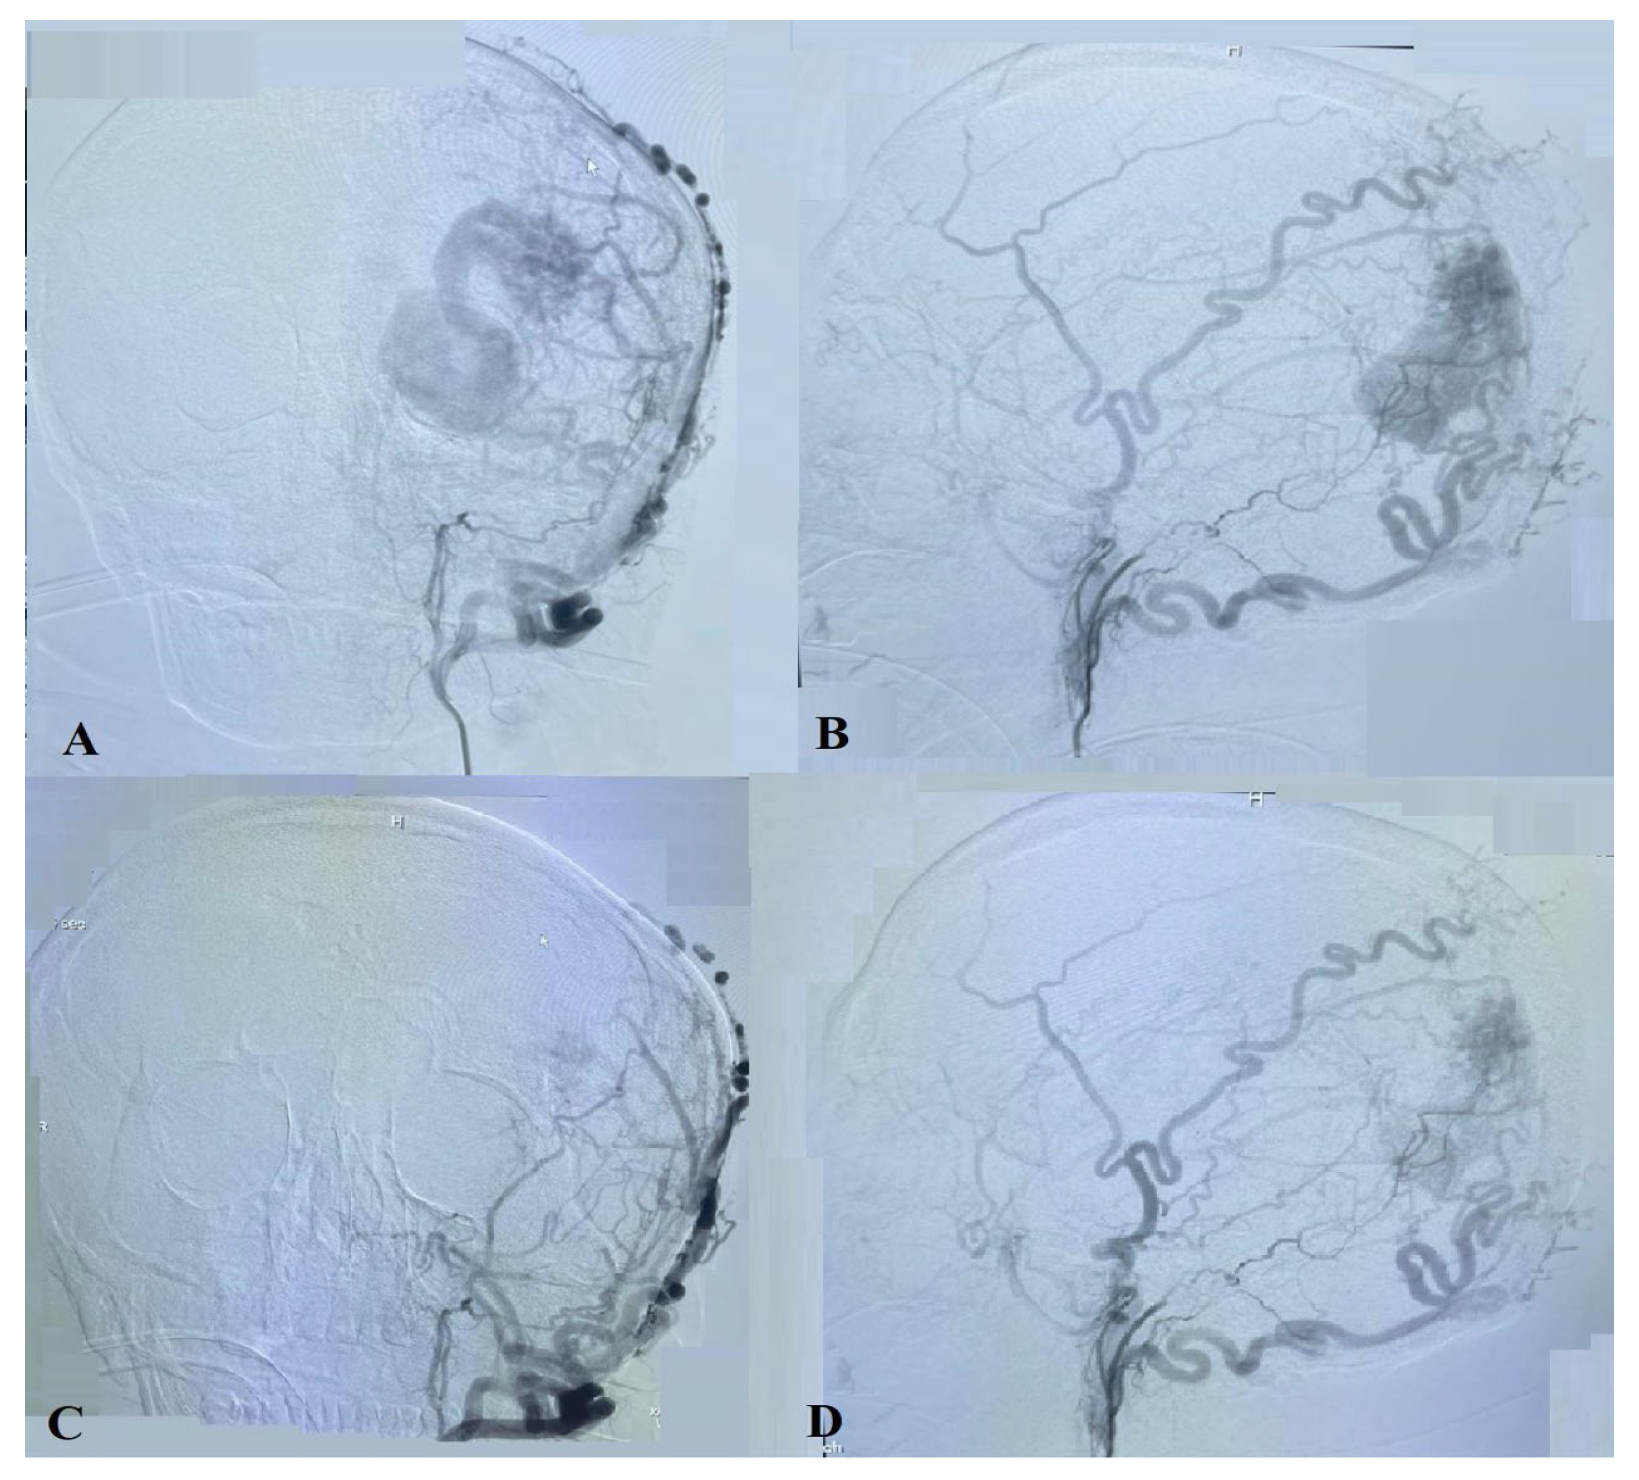

2.1. Diagnostic Procedures